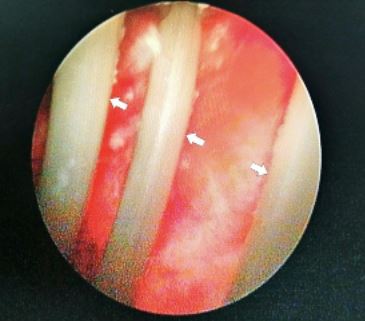

The strange insertion was carried out “based on s3xual pleasure and gratification,” and the wire that had lodged itself in his bladder was “visible and quickly identified” by the hospital team.

The wire had been coiled and fortunately not attached to the bladder wall, with an extraction carried out using grasping forceps, while the earphone wire was said to be 2-3mm in size and 80cm in length.